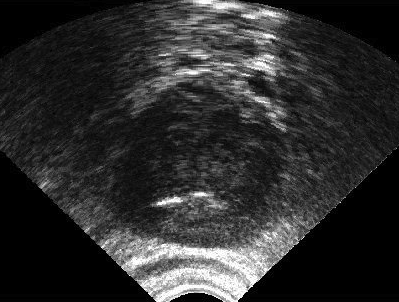

IV-A Image Data: Synthetic TRUS Images

It is a considerable challenge to validate any approach to computed consensus contouring. The ultimate test, to be sure, is to measure the accuracy of the computed consensus contour 𝐂𝐂\mathbf{C}. However, this depends on assessing the quality of the consensus. Unless there is a “gold-standard segment” G𝐺G for each image, reliable validation will not be straightforward, and any particular observation will be inconclusive. Of course, this is not feasible with real images, for which there is no gold standard. Hence, we generated synthetic images whose gold segments were known a priori. For this reason, we used synthetic images that simulate transrectal ultrasound (TRUS) images.

TRUS images of prostates may be used to both diagnose and treat prostate diseases such as cancer. Starting with a set of prostate shapes P1,P2,,Pmsubscript𝑃1subscript𝑃2subscript𝑃𝑚P_{1},P_{2},\dots,P_{m}, we created random segments Gisubscript𝐺𝑖G_{i} through combinations of those priors, adding noise along with random translations and rotations, and we distorted the results with speckle noise and shadow patterns. Each image Iisubscript𝐼𝑖I_{i} is thus created from its gold Gisubscript𝐺𝑖G_{i}. Consequently, we can simulate k𝑘k user delineations Si1,Si2,,Siksuperscriptsubscript𝑆𝑖1superscriptsubscript𝑆𝑖2superscriptsubscript𝑆𝑖𝑘S_{i}^{1},S_{i}^{2},\dots,S_{i}^{k} by manipulating Gisubscript𝐺𝑖G_{i} via scaling, rotation, and morphological changes, and we can simulate edits by running active contours with variable user-simulating parameters. The variability of user delineations was simulated according to several factors: error probability ([0,0.05]00.05[0,0.05]), anatomical difficulty (=0.2absent0.2=0.2 out of [0,1]01[0,1]), and the scaling factor for morphology (form 1×1111\!\times\!1 to 21×21212121\!\times\!21). The user was modelled according to the level of experience (a random number from (0,1]01(0,1]), the user’s attention (a random number from [0,1]01[0,1]), and the user’s tendencies in terms of the segment size (a random number from [1,1]11[-1,1]), whether tending to draw contours that are relatively small (1absent1\rightarrow\!-1) or large (+1absent1\rightarrow\!+1).

We generated 500 images from their corresponding gold-standard images. Furthermore, we generated 20 different segments for each image, assuming that there were 20 users. Figure 4 shows three examples of real and synthetic TRUS images. One should bear in mind that the purpose here was not to simulate the images realistically, but rather to have a base from which to generate variable segments from a perfect segment. Figure 5 shows an example of the gold segments and simulated user contours. The variability, coupled with the gold segment, is what is needed to validate our approach.

Figure 4: Sample TRUS (top) and simulated images (bottom).